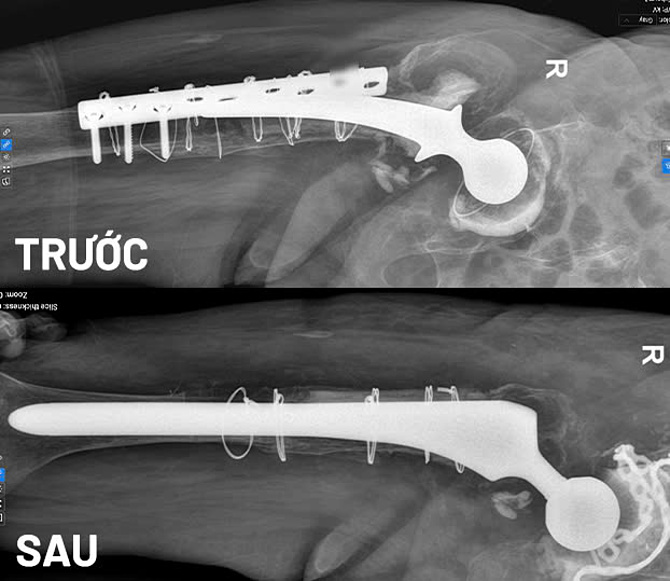

Bà An cao tuổi,thể trạng yếu,suy tim nên các bác sĩ khoa Tim mạch,Gây mê hồi sức,Chấn thương chỉnh hình hội chẩn để đưa ra phương án điều trị an toàn nhất. Chụp X-quang trước mổ cho thấy một phần đầu trên xương đùi và phía ổ cối bị tiêu xương nghiêm trọng,có vị trí gần như đứt rời,rất khó tái tạo.

Êkíp quyết định ghép xương tái tạo khung chậu và đầu trên xương đùi,sau đó thay khớp háng. Phẫu thuật này phức tạp,thời gian kéo dài,nhưng bệnh nhân có thể tập phục hồi sớm,chi phí điều trị hợp lý.

Hình ảnh chụp MRI trước và sau khi bệnh nhân thay khớp háng lần thứ tư. Ảnh: Bệnh viện Đa khoa Tâm Anh